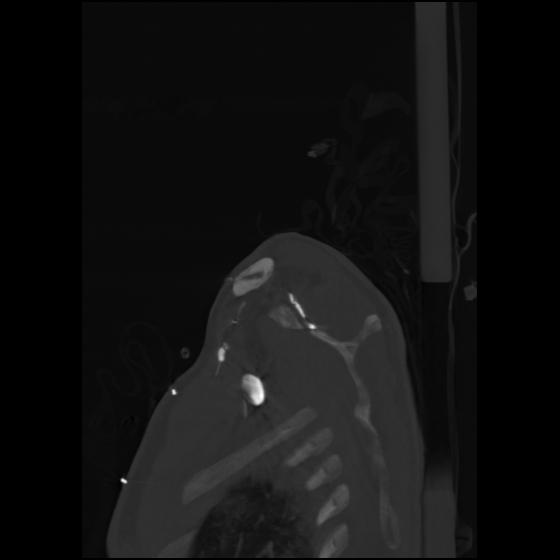

24 ANGIO,CE,Sag-MIP,5.000,ANGIO,Sag-MIP,